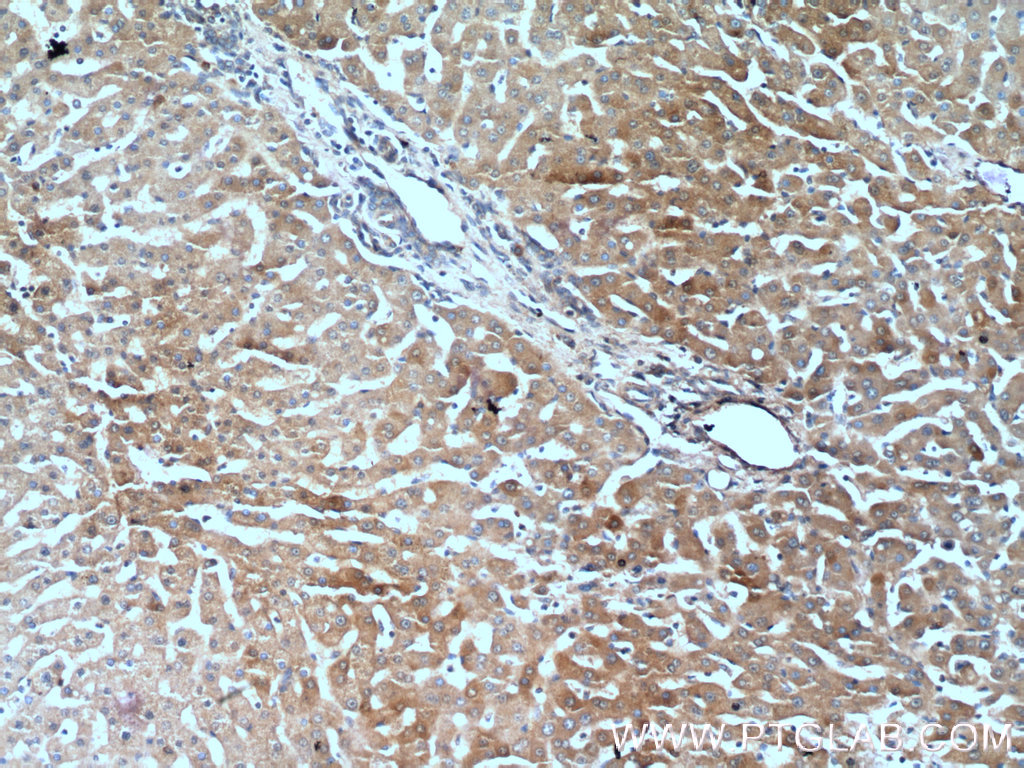

| Positive IHC detected in | human liver tissue, mouse kidney tissue Note: suggested antigen retrieval with TE buffer pH 9.0; (*) Alternatively, antigen retrieval may be performed with citrate buffer pH 6.0 |

22263-1-AP targets Polycystin 1 in IHC, ELISA applications and shows reactivity with human, mouse samples.

| 经测试应用 | IHC, ELISA Application Description |